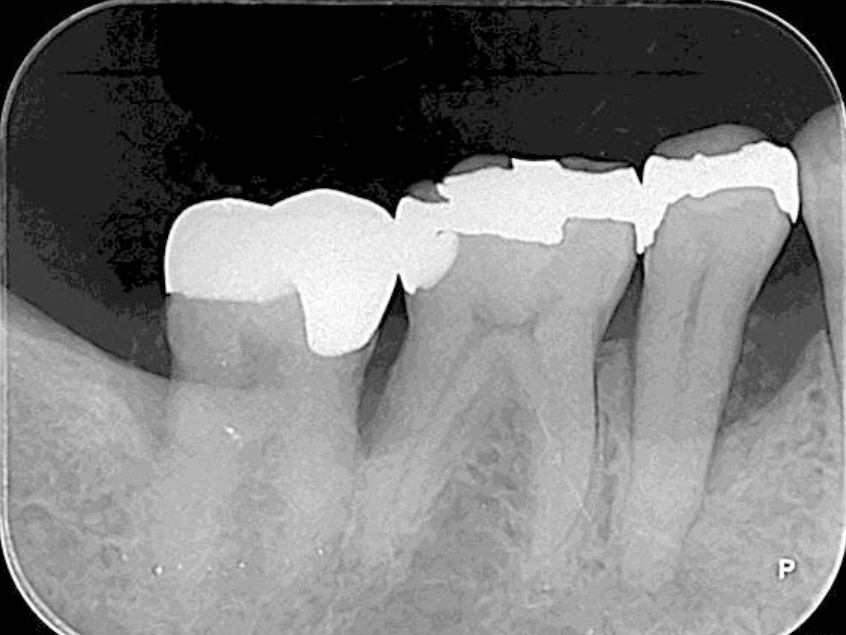

歯周基本治療・歯周外科処置を行なった症例

初診時

歯周基本治療後

歯周外科処置

歯周外科処置後

初診時年齢:30代女性

治療:歯周病治療

治療法:歯周基本治療、歯周外科処置

治療期間:1年6ヶ月

費用:保険診療

リスク・副作用:歯周外科処置後に出血、腫れ、あざが出ることがありますが時間とともに治ります。術後3週間程度噛んだときの痛みや歯が浮いた感じがすることがあります。術後の歯肉退縮により知覚過敏が生じることがあります、時間とともに落ち着くこともありますが症状が続く場合は根管治療を行います。